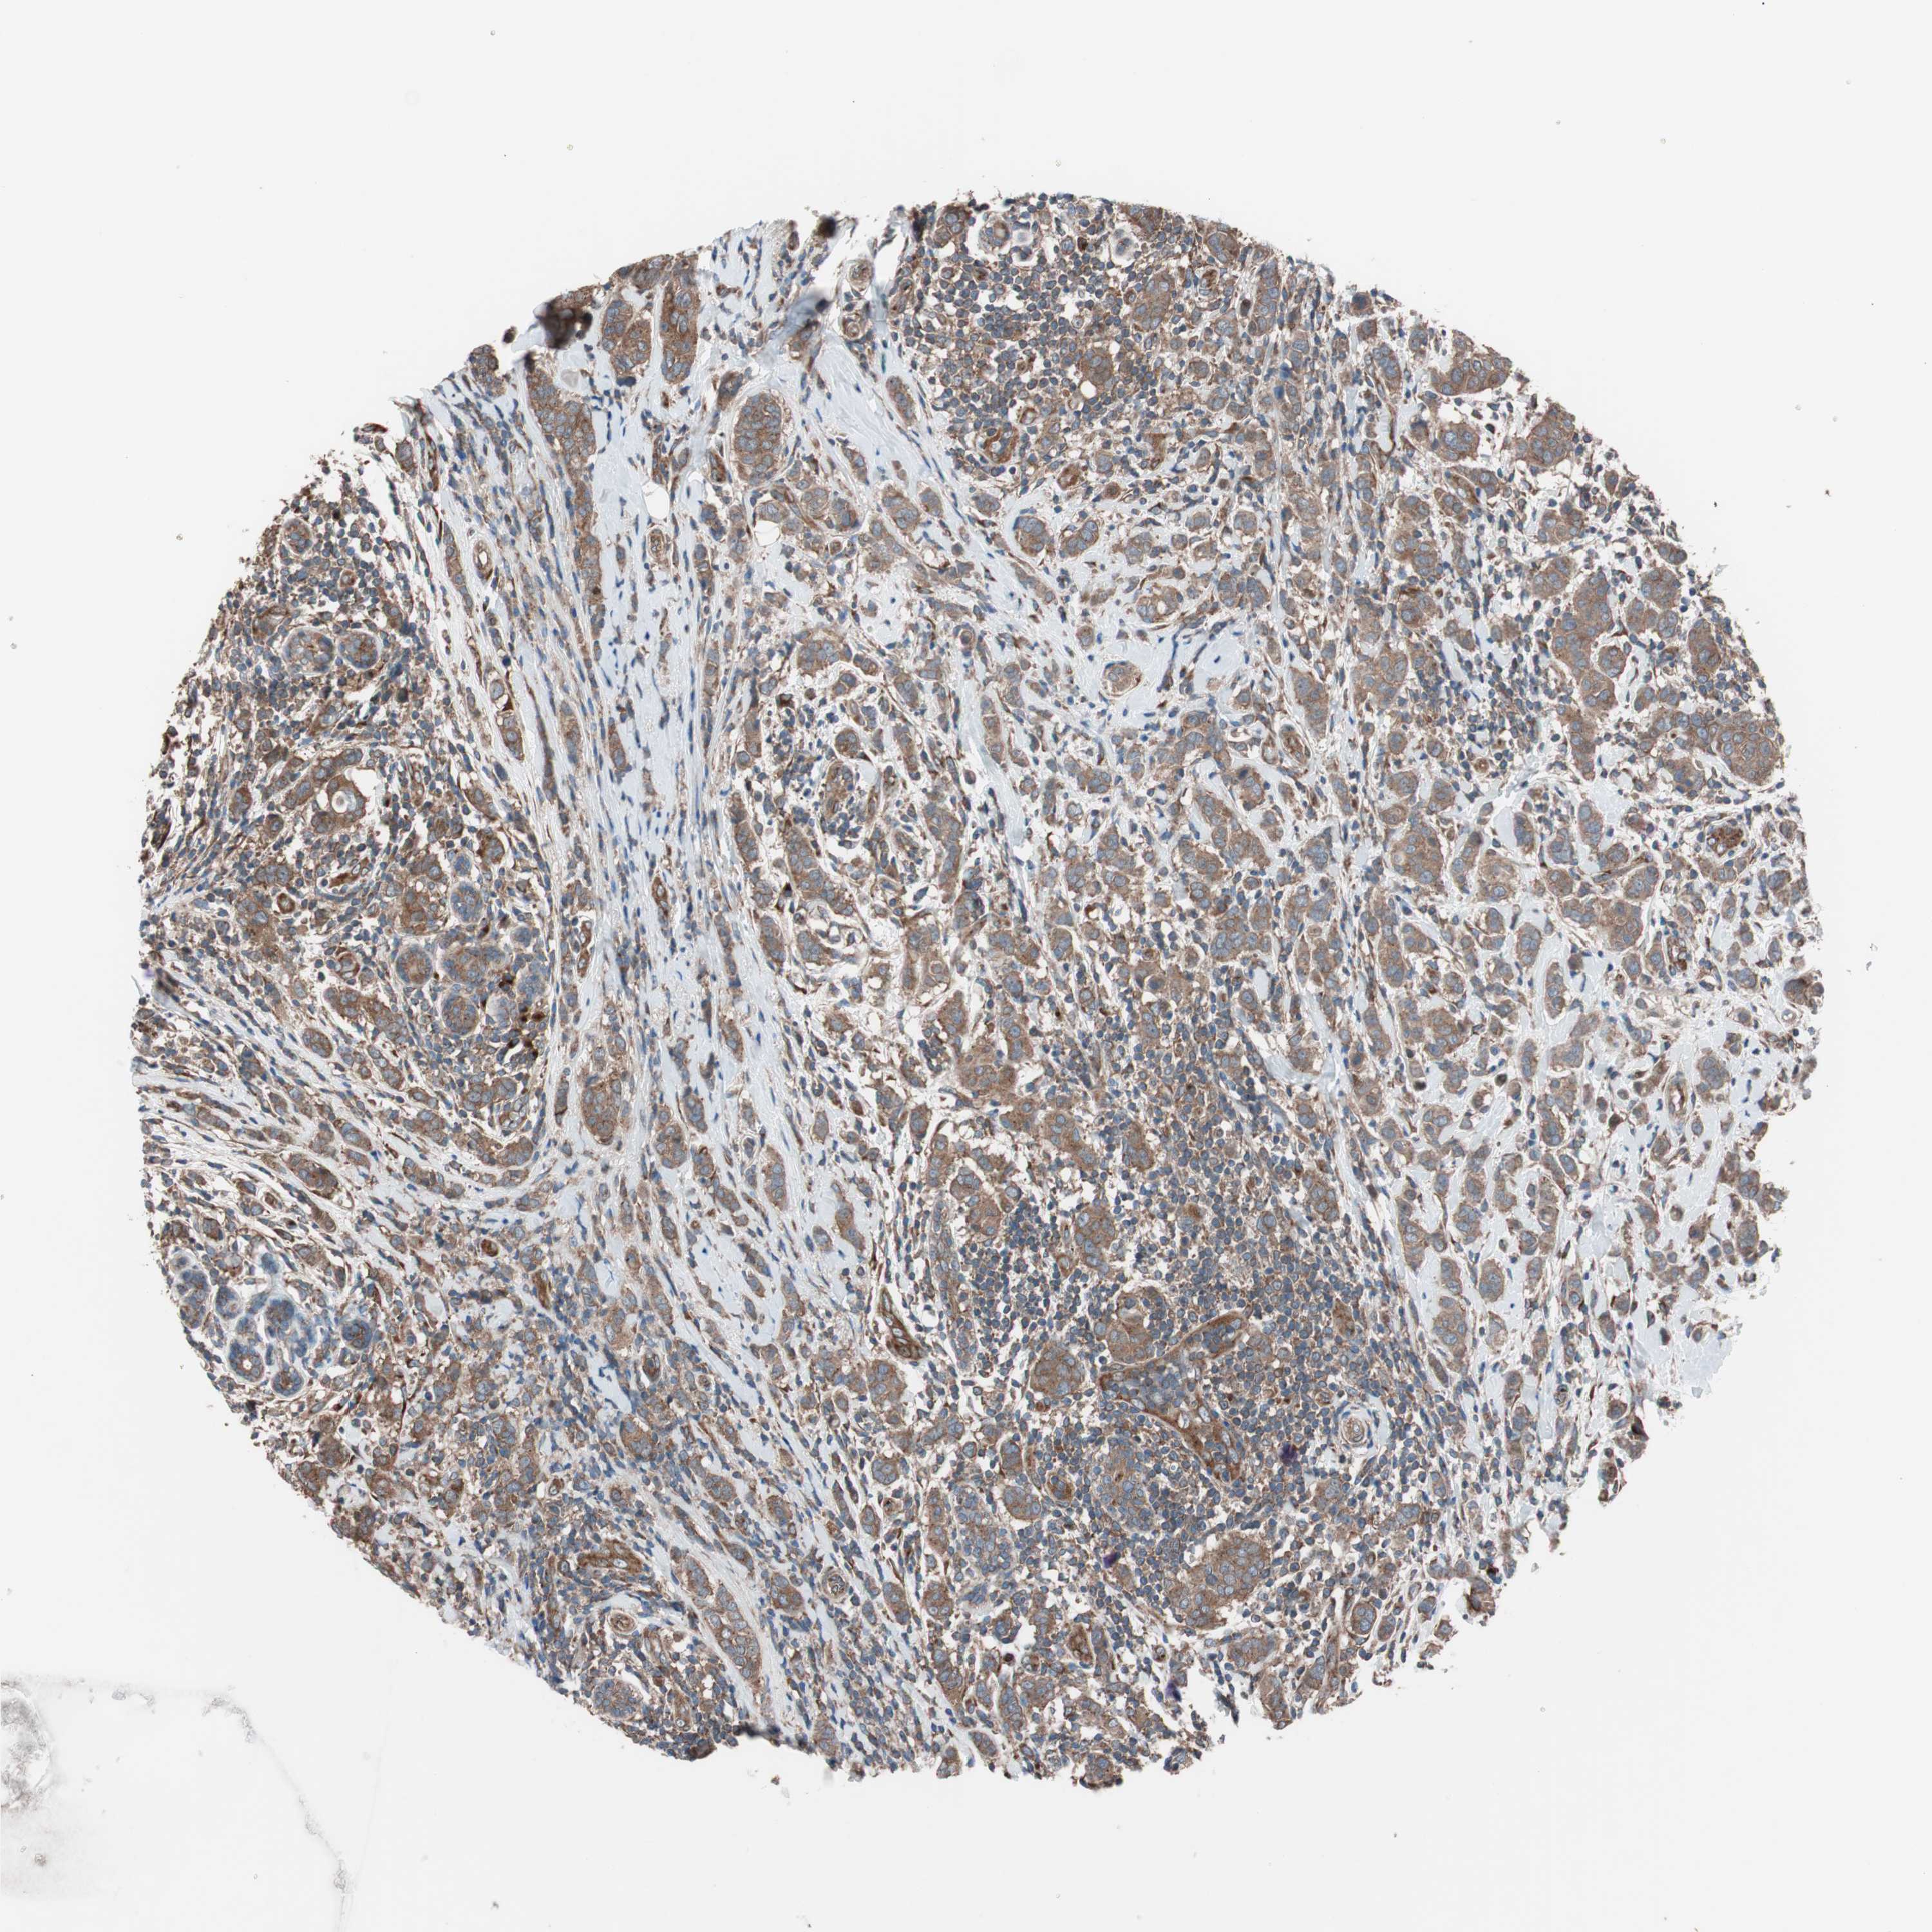

BRCA TCGA BRCA VALIDATION PROTEIN EXPRESSION

ANTIBODIES

AND

VALIDATION